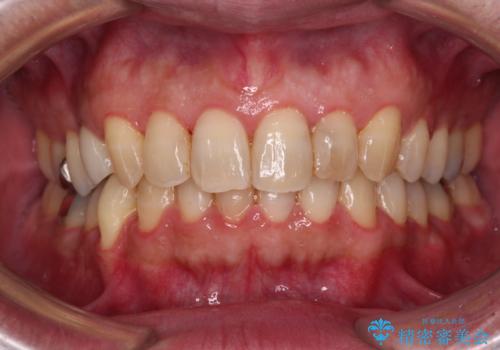

- 外に飛び出した側方の歯と、前歯のデコボコを気にして来院された患者様です。

IPR(歯と歯の間を削る)によってデコボコが解消するように設計し、インビザラインにより治療を行うこととしました。

治療途中で1年半以上通院されない時期があったため、後戻りが生じたことで治療期間が長くなってしまいました。

親知らずを抜去したことで、下顎のデコボコがきれいに解消されました。